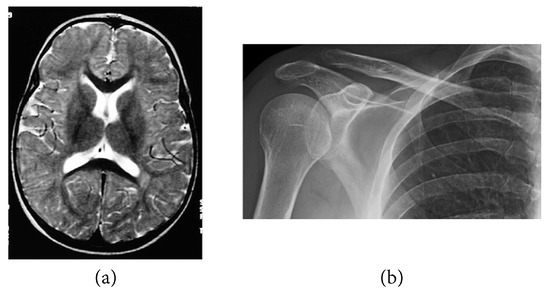

The following numerical results are proposed: Figure 2 presents the original grayscale images for (a) X-ray film of the brain and (b) X-ray film of the right shoulder. Figure 3 and Figure 6 are blurred X-ray films of the brain and the right shoulder images with filtering M i x in the part of degradation of Figure 1. In this example, we set N = 4 . So, we have M 1 x , M 2 x , M 3 x , and M 4 x . Figure 4a, X-ray films of the brain and the right shoulder images were obtained via Theorem 2. Figure 4b, X-ray films of the brain and the right shoulder images were obtained via Theorem 3.1 in [16] (Khuangsatung and Kangtunyakarn’s method). Figure 9 is an X-ray film of the brain image that was recovered via the proposed method that was tuned for the parameter λ.

Figure 2. Original grayscale images. (a) X-ray film of the brain image and (b) X-ray film of the right shoulder image.